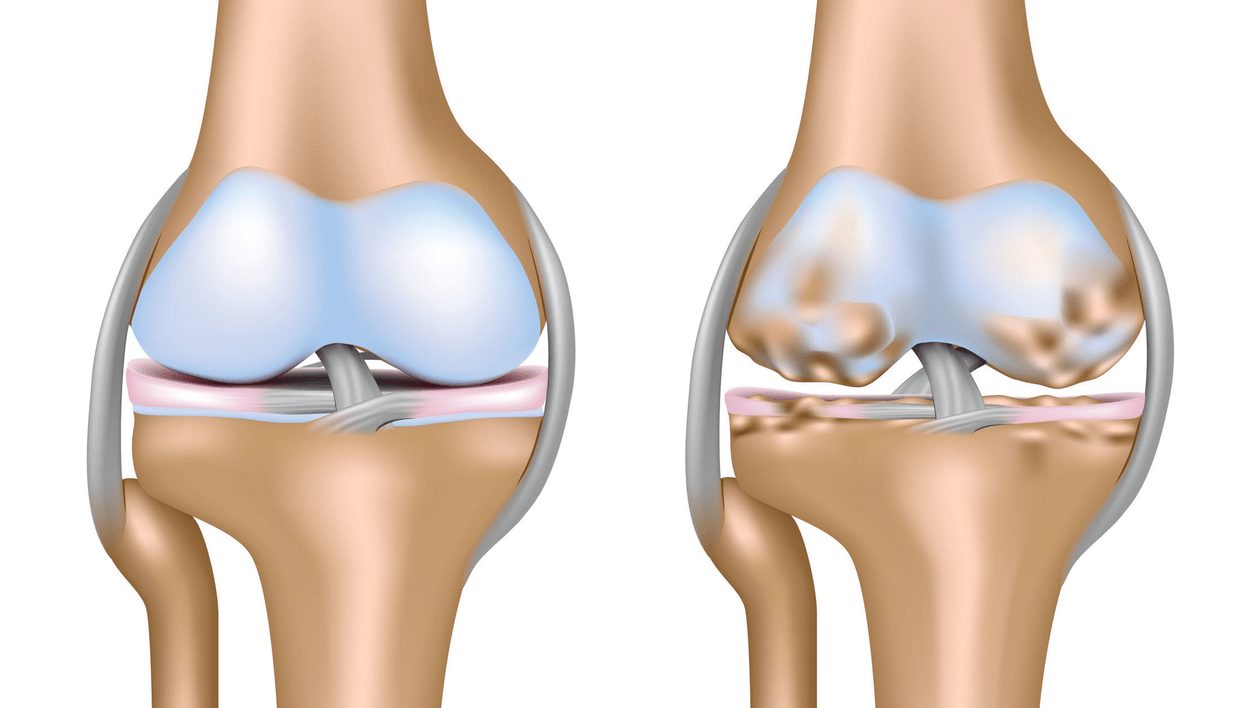

Arthrosis of the knee joint (gonarthrosis)is a chronic progressive disease of the knee joints with damage, thinning and destruction of its cartilage part (articular surfaces of the femur and tibia), as well as damage to the subchondral bone.From the studies (arthroscopy and MRI) it has been proven that in addition to damage to the articular cartilage, the menisci and synovial membrane are also involved in the process.Gonarthrosis is one of the most common orthopedic pathologies.It has its synonyms - osteoarthritis (OA), deforming arthrosis.The disease is an important socio-economic problem, as it is widespread and significantly worsens the quality of life of patients due to constant pain and, in addition, becomes a cause of high disability.

Until the mid-eighties of the last century, there was no unified definition of the disease.Only in 1995, the osteoarthritis committee of the American College of Rheumatology characterized the disease as the result of mechanical and biological factors leading to an imbalance between the processes of degradation and synthesis of the extracellular matrix of articular cartilage.As a result, fiber disintegration and degeneration occurs, cracks, osteosclerosis and compression of the cortical layer of the subchondral bone are created, osteophytes and subchondral cysts grow.

With arthrosis (osteoarthrosis), in addition to the progressive destruction of cartilage, the loss of its elasticity and shock-absorbing properties, the bones are gradually involved in the process.Under load, sharp edges (exostoses) appear, which are mistakenly considered "salt deposits" - with classic arthrosis, salt deposition does not occur.As osteoarthritis progresses, it continues to "eat away" the cartilage.Then the bone is deformed, cysts are formed there, all joint structures are affected and the leg bends.

In the second stage, the cartilage layer becomes significantly thinner, and in some places it is completely absent.Osteophytes appear along the edges of the articular surfaces.The qualitative and quantitative characteristics of the joint synovial fluid change - it becomes thicker, more viscous, which leads to a deterioration of its nutritional and lubricating properties.The pain is more prolonged and severe, and there is often a popping sound when moving.There is mild or moderate limitation of motion and mild joint deformity.Taking analgesics helps relieve pain.

Gonarthrosis, stage III

Absence of cartilage in the most affected areas, severe sclerosis (hardening) of the bones, many osteophytes and a sharp narrowing or lack of joint space.Pain is almost constant, walking is impaired.Mobility is very limited, and joint deformity is evident.NSAIDs, physiotherapy and other standard methods of treating knee arthrosis are ineffective.